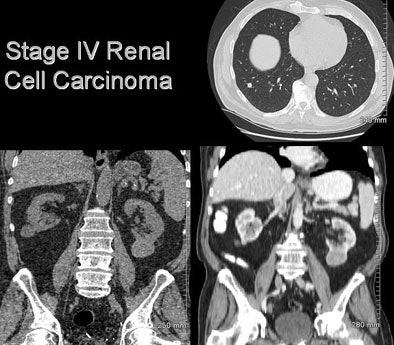

![]() |

| A man in his 70s underwent CT colonography screening; MDCT revealed a large renal mass. Workup also revealed multiple lung nodules. He was diagnosed with metastatic renal cell carcinoma; however, no intervention has been performed due to multiple comorbidities, and the patient has done well. |